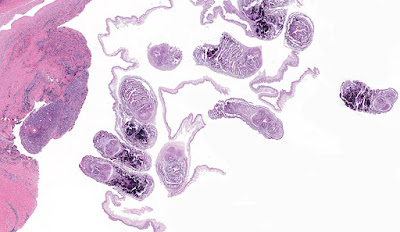

This week's case was donated by Dr. Paul Valenstein, and it is a beautiful example of an uncommon finding. It is an eyelid biopsy from a 6-year-old African child.

The non staining hooklets of the invaginated scolex and the convoluted spiral canal indicated that this is a case of Cysticercus cellulosae. To tell the truth, I got it from the previous cases on the Blog. Thank you Dr. Pritt. Florida Fan

The multiple scoleces that seem to come from a unique germinative layer make me think to a case of coenurosis, due to Taenia serialis or Taenia multiceps.

I agree with coenurosis - probably caused by T. multiceps as it involves the eye, but not excluding T. serialis as skin is involved as well (eyeLID).

Hi Unknown, Schisto can be ruled out by the fact that we can clearly see hooklets. Also the abundant presence of calcarous bodies indicates that a cestode is involved here! Interesting case for sure!